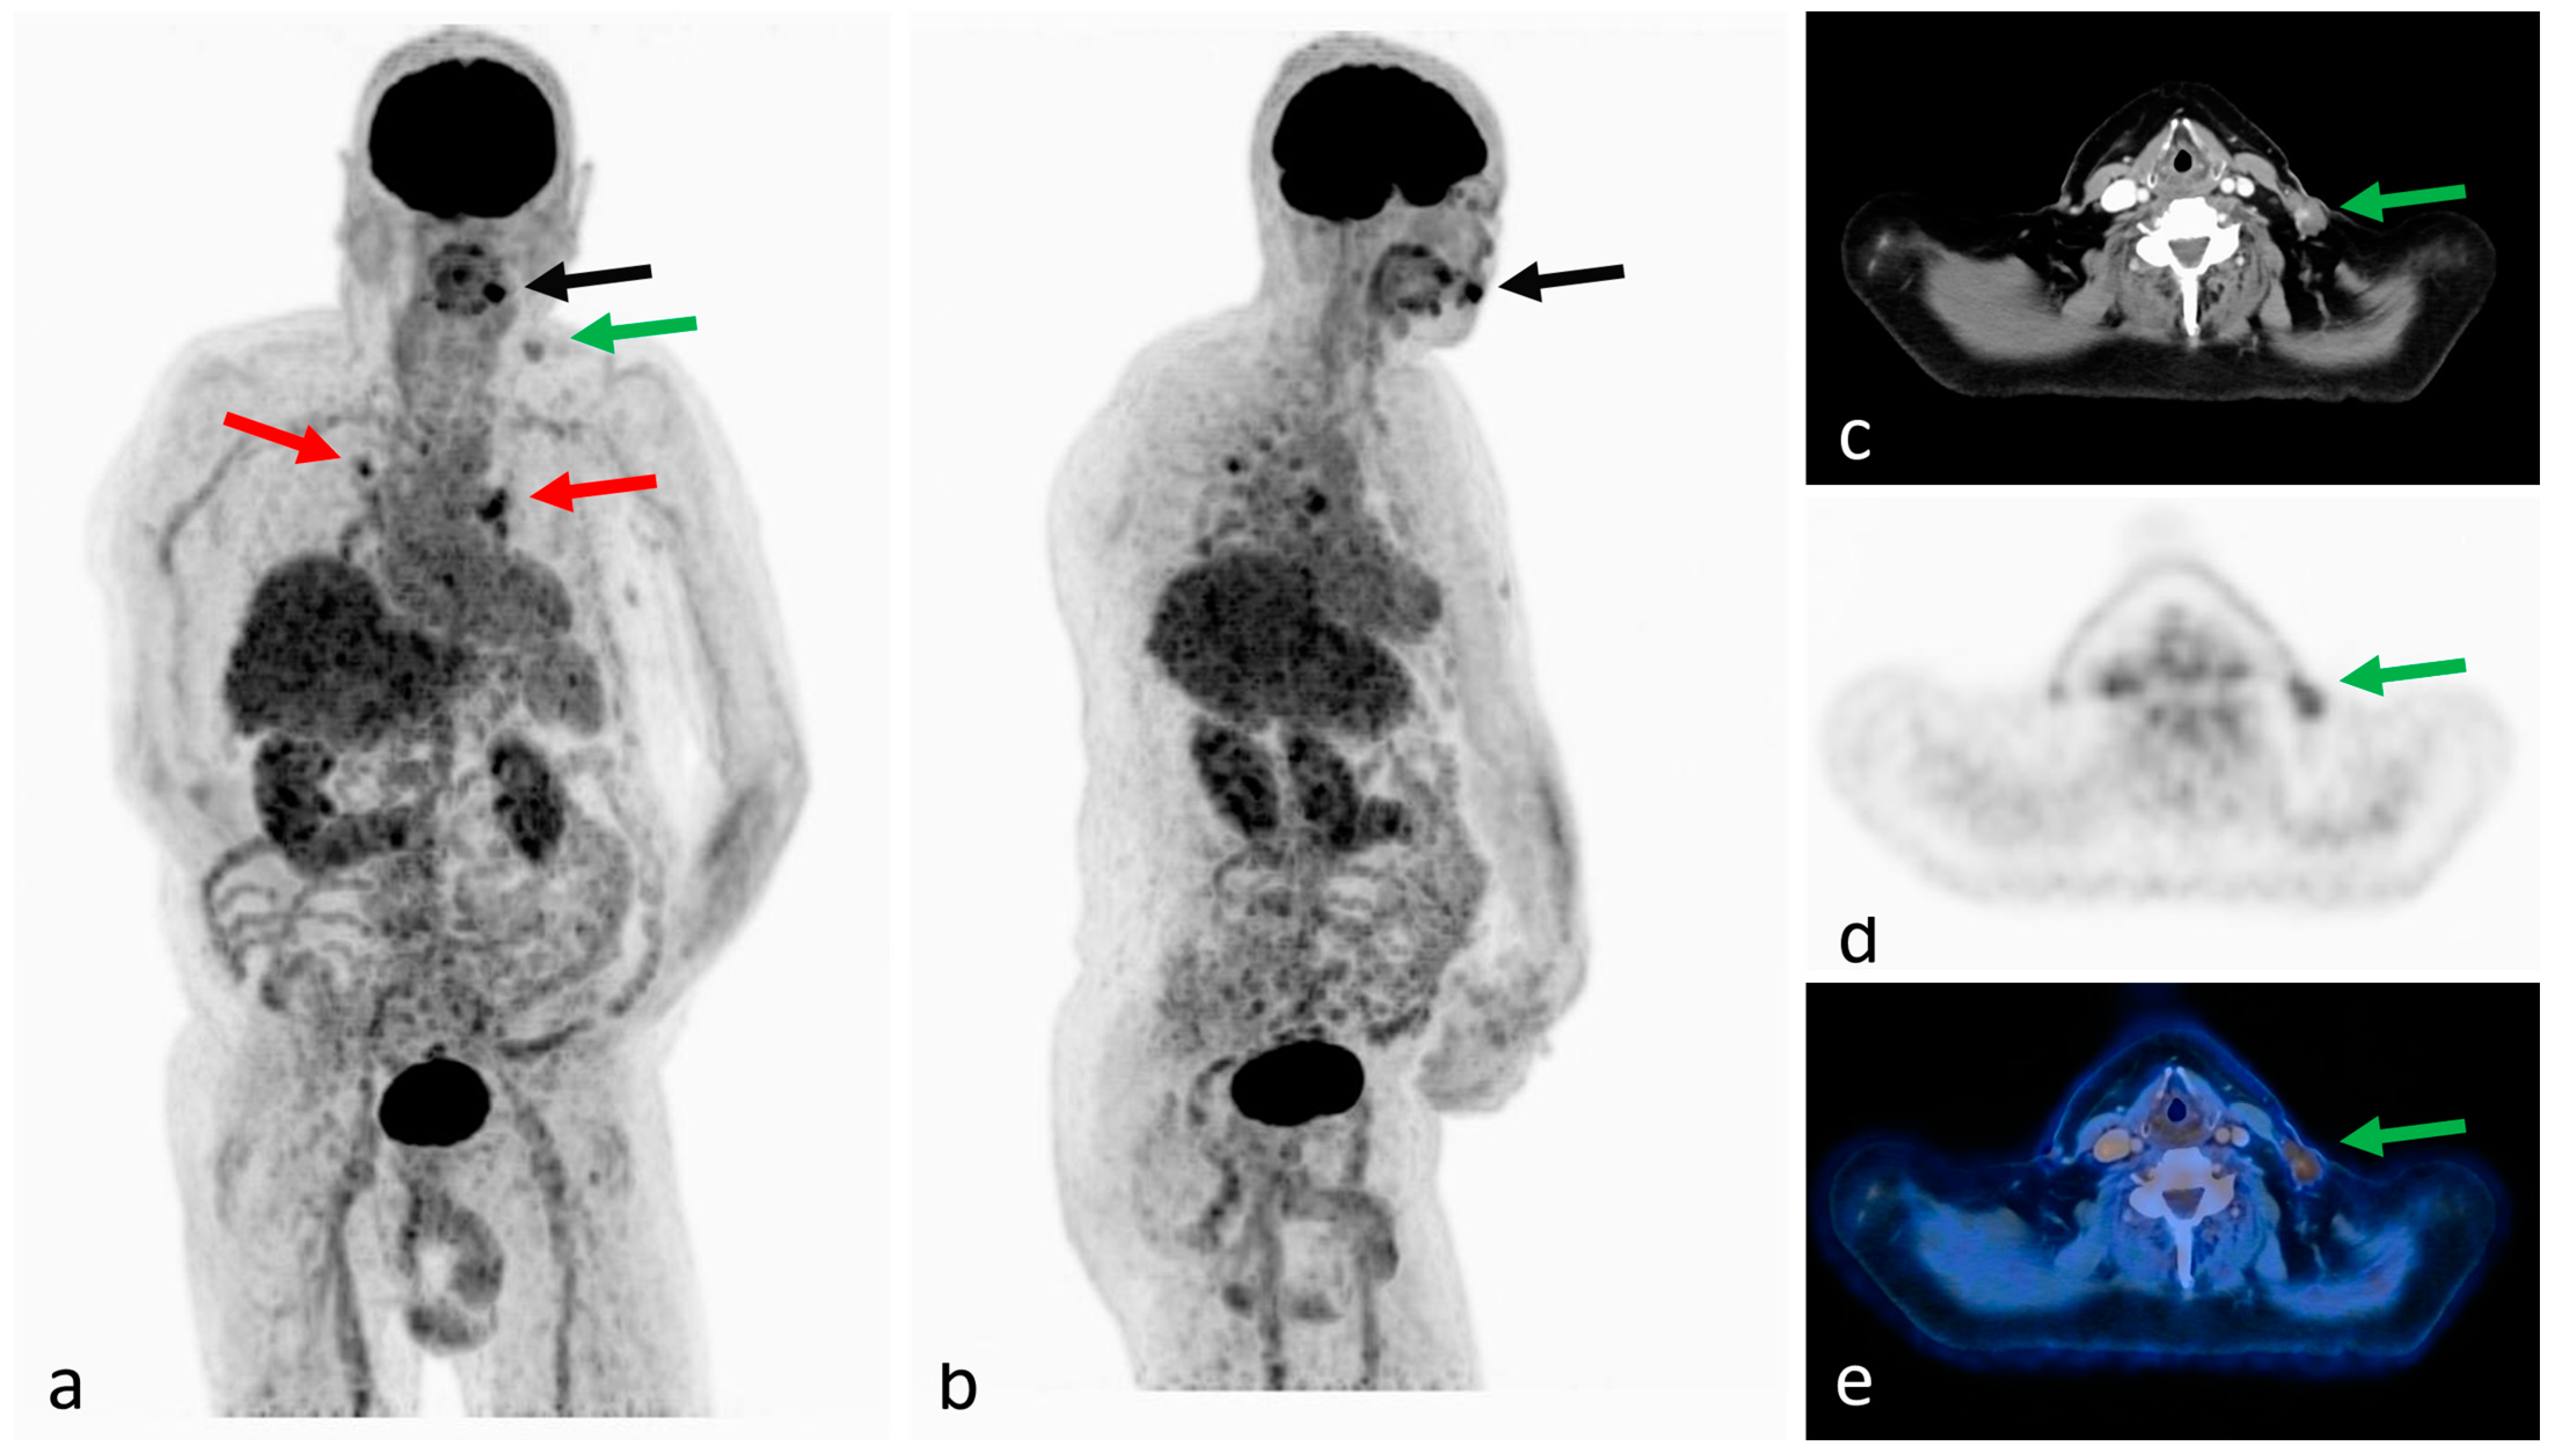

2. Case Report